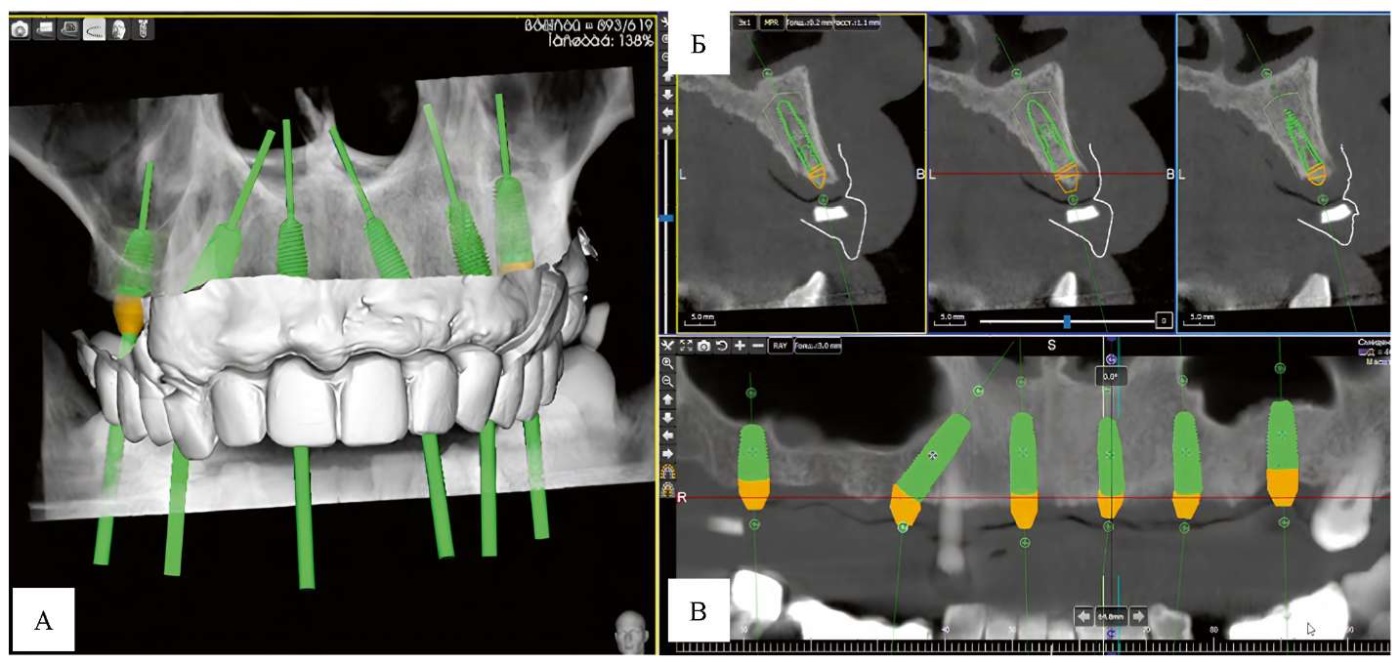

Для планирования хирургического этапа лечения было выполнено внутриротовое сканирование зубных рядов пациента при помощи сканера Primescan (Dentsply Sirona, США). Далее полученные stl-файлы зубных рядов вместе с данными конусно-лучевой компьютерной томографии исследования пациента в виде dcm-файлов были загружены в программу для планирования постановки имплантатов 3Diagnosys (3DIEMME, Италия).

Коронки искусственных зубов на частично-съемном протезе пациента использовались в качестве ориентира при позиционировании имплантатов, так как имеющийся частично-съемный протез устраивал пациента с эстетической и функциональной точек зрений (рис. 5).

Рис. 5. Виртуальное планирование операции дентальной имплантации пациента А. в программе 3Diagnosys: А — модель коронки искусственных зубов на частично-съемном протезе пациента использовались в качестве ориентира при позиционировании имплантатов с наложением на снимки конусно-лучевой томографии; Б — позиционирование имплантатов в альвеолярном отростке верхней челюсти в программе-моделировщике на сагиттальном срезе; В — виртуальное позиционирование имплантатов с наложением на ортопантомограмму

Примечание: фотографии выполнены авторами.

Fig. 5. Virtual planning of dental implant surgery for patient A. in the 3Diagnosys software: A — a model of artificial tooth crown on the patient’s partial removable denture was used as a reference point for implant positioning with superimposition on cone beam computed tomography images; Б — positioning of implants in the maxillary alveolar process in the simulation software on a sagittal section; В — virtual positioning of implants superimposed on an orthopantomogram

Note: The photograph was taken by the authors.